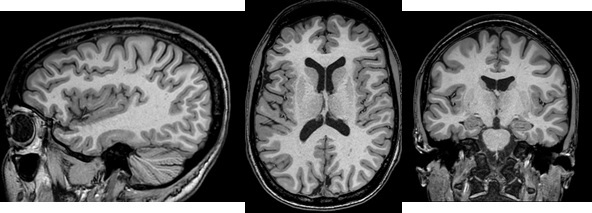

Figure 1. MP-RAGE head images